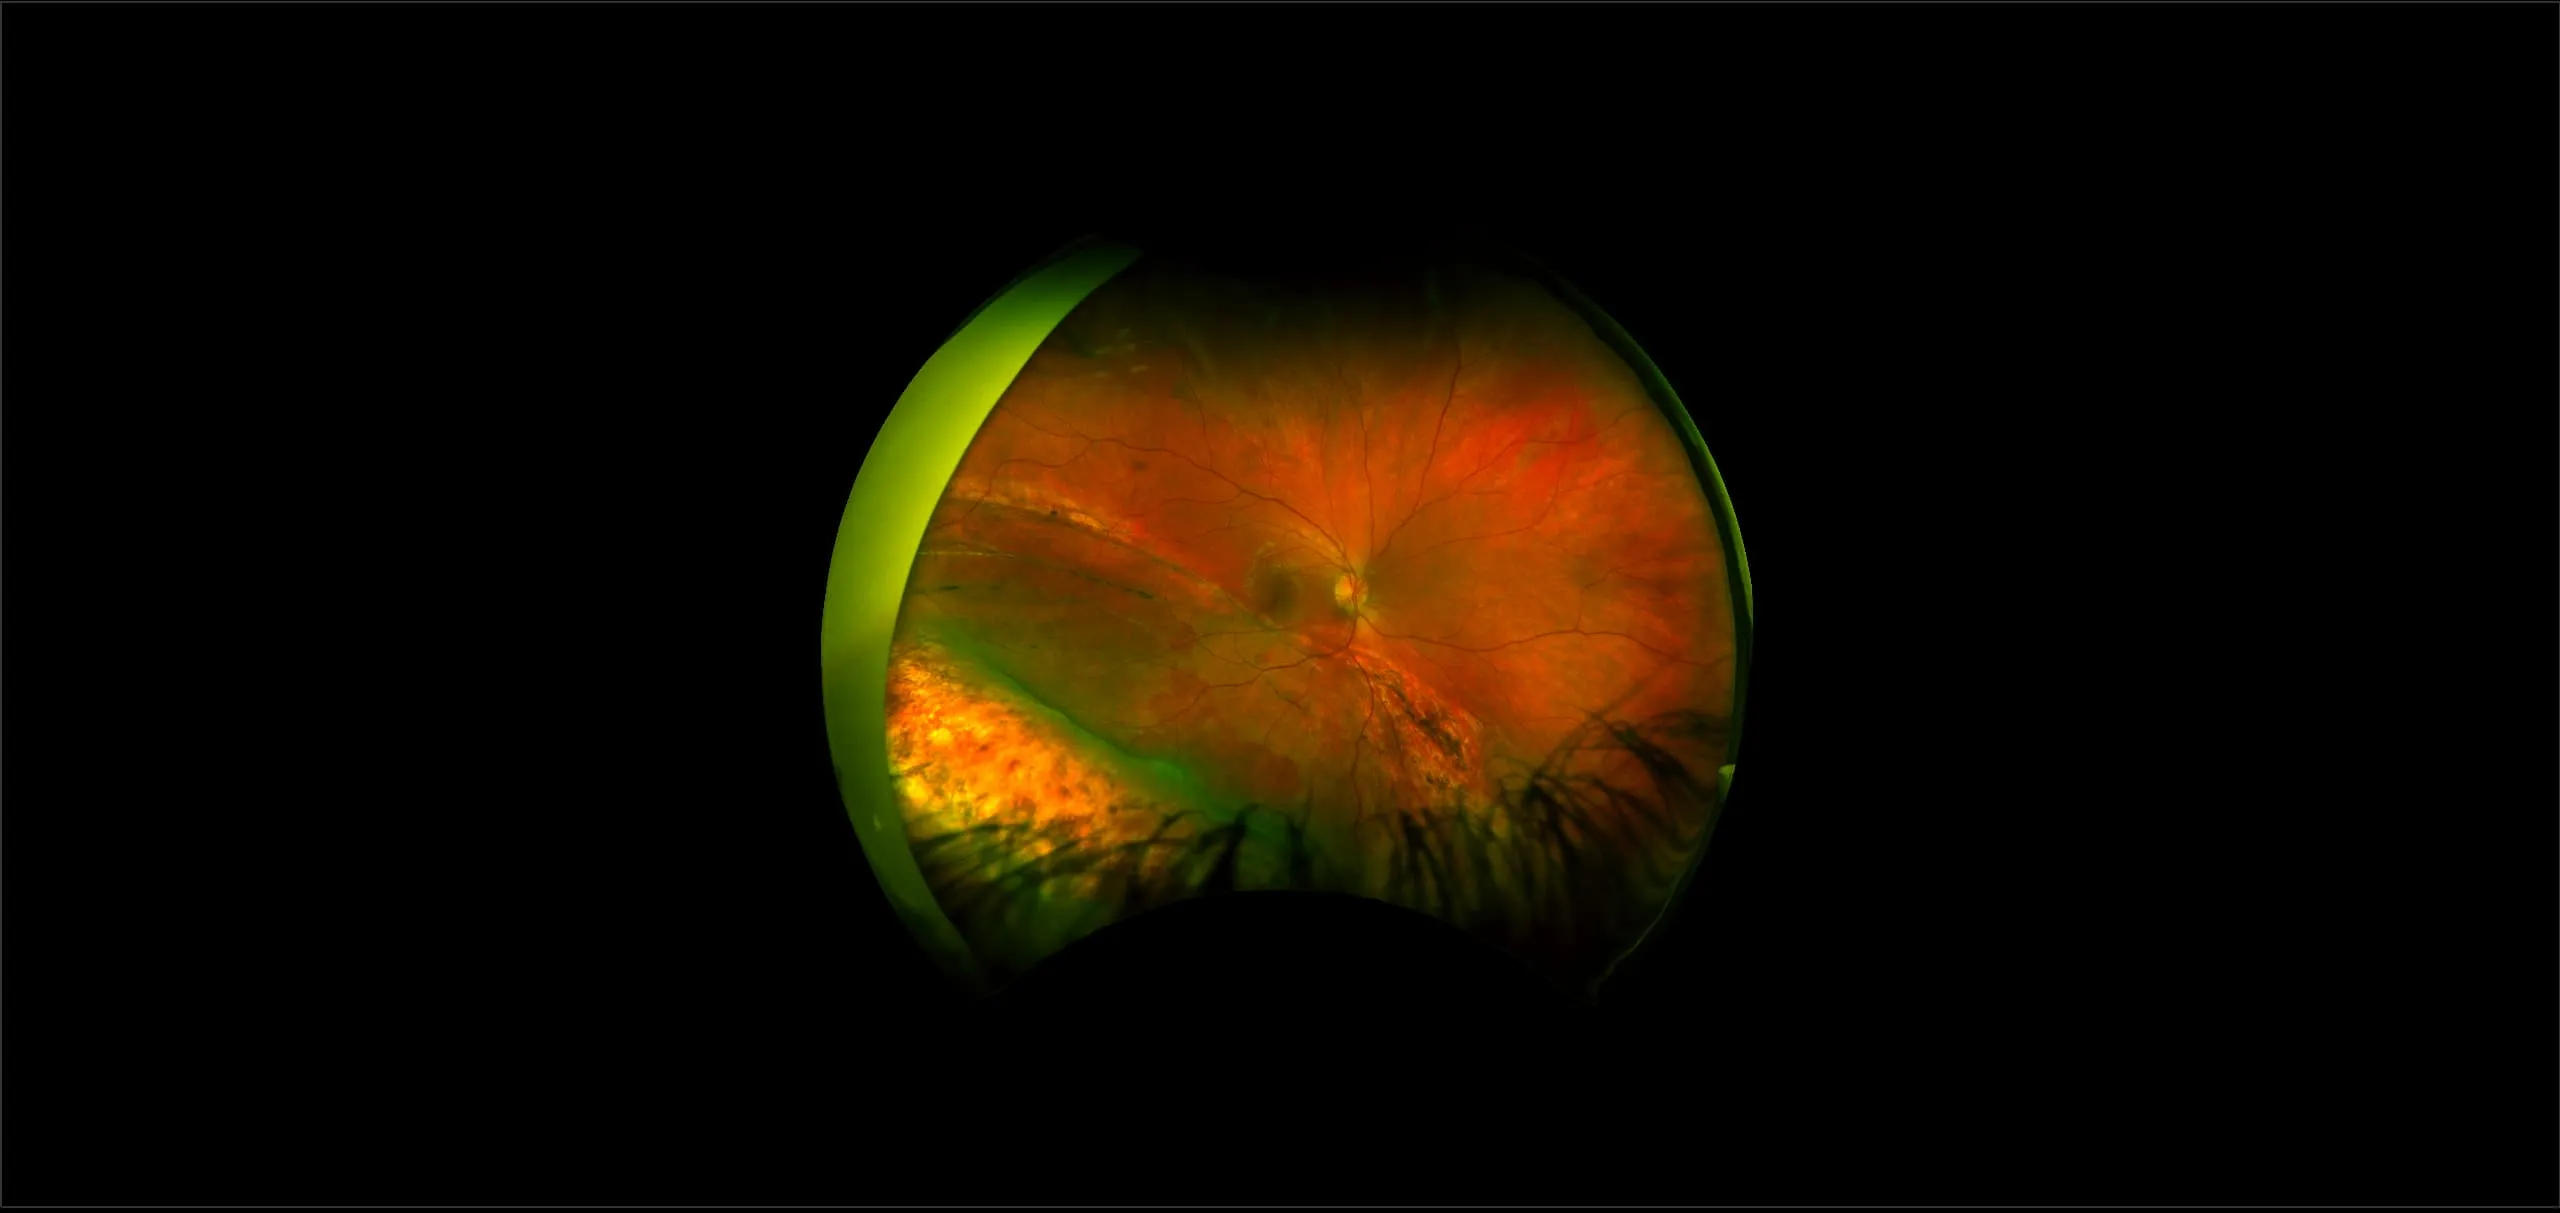

This material is designed as a searchable reference resource to support clinical decision-making. The information contained here should be used as general guidance when viewing optomap and OCT images from Optos devices. The differential diagnosis should be made under the direction of the responsible physician. These images were taken on the latest ultra-widefield optomap devices.

optomap Recognizing Pathology is searchable by pathology and/or optomap image modality. You may search by multiples of each selection. Each individual case is represented by the accompanying thumbnail image. Most cases include several different optomap image modalities. To view a full description of the case, please click on the thumbnail. Each image in the case will be made available through our OptosAdvance software which provides multi-dimensional visualization of digital images to aid in the analysis of anatomy and pathology. Support and pathology definitions can be found by selecting one of the buttons, above. Should you have questions, please complete the form below.